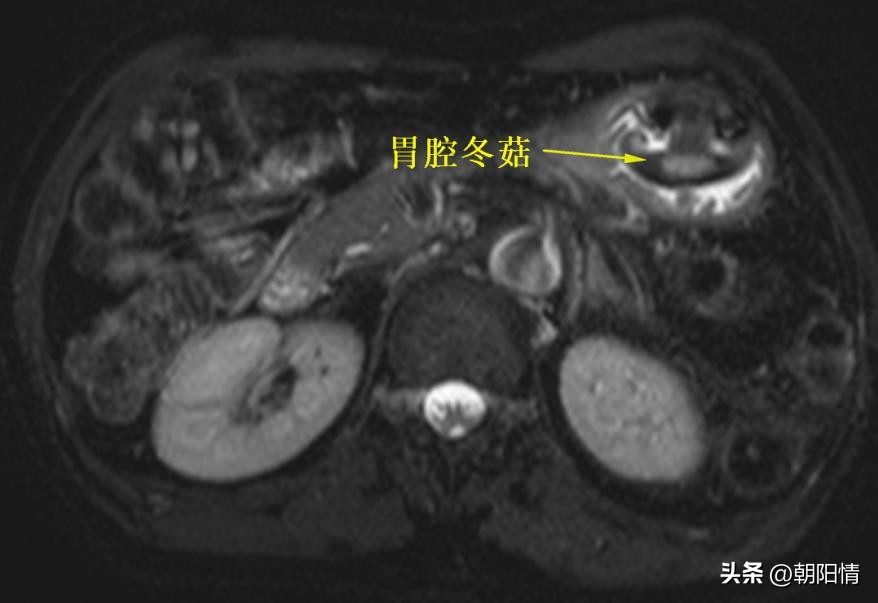

Case6:老年男性,有胃部分切除术病史,消化功能减弱。MRI检查胃腔见冬菇影。